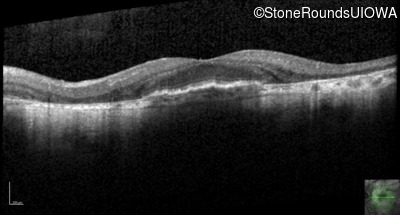

AR Stargardt Disease (IIA)

Age at visit: 51 years

This 51 year old woman first experienced some abnormality in her distance vision when she was 27 years old. She feels that her vision has been stable since that time.

Diagnosis & molecular findings

Disease Gene Allele 1 variant(s) Allele 2 variant(s) Inheritance mode

AR Stargardt Disease ABCA4 Gly1507Arg GGG>AGG IVS42+1 G>A AR